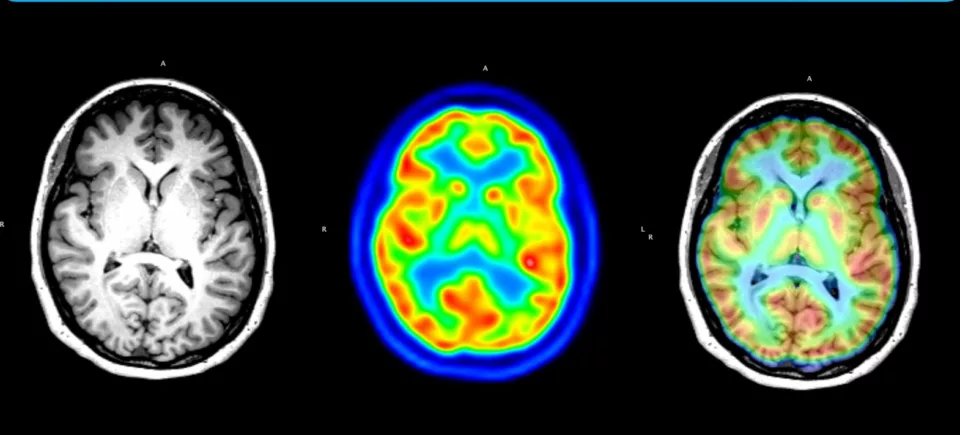

La invención, desarrollada en colaboración con la Unidad de Imágenes Cuantitativas Avanzadas (UNICA), y el equipo multidisciplinario del Centro Avanzado de Epilepsia de CAS, ambas pertenecientes a la Clínica Alemana de Santiago, adquiere especial relevancia en el campo de la epilepsia, un trastorno eléctrico del cerebro que afecta aproximadamente al 1% de la población chilena, pudiendo alcanzar hasta el 4% en otras regiones. La del tipo refractaria, es altamente invalidante y sólo puede ser tratada efectivamente mediante cirugía. Para estudiarla, se suele utilizar el examen PET, y la resonancia magnética.

La nueva invención patentada del CICS, combina el PET con la resonancia magnética, y es la que permite construir la base de datos de imágenes cerebrales, a través de la cual es posible determinar, en base a criterios estadísticos, la localización específica de la lesión.